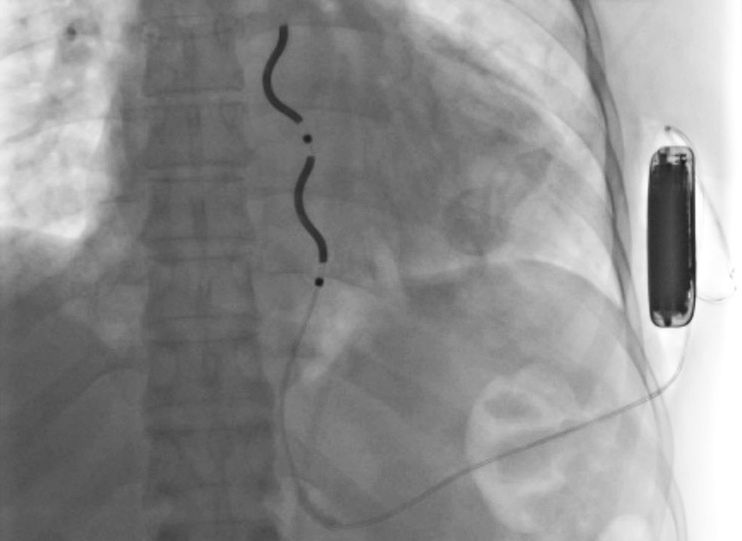

EV-ICD składa się z elektrody oraz generatora impulsów. Jego zadaniem jest wykrycie niebezpiecznej arytmii i natychmiastowe przerwanie jej za pomocą impulsu elektrycznego, zanim dojdzie do poważnych, nieodwracalnych zmian w organizmie. W odróżnieniu od tradycyjnych defibrylatorów, w których elektroda wprowadzana jest przez żyły bezpośrednio do wnętrza serca, w nowym rozwiązaniu elektroda znajduje się pod mostkiem, a generator umieszczany jest pod skórą w okolicy lewej pachy.

Pierwszym pacjentem, który skorzystał z nowej technologii w Poznaniu, był 47-letni mężczyzna po wielokrotnych zatrzymaniach krążenia. Po skutecznej reanimacji w karetce i na szpitalnym oddziale ratunkowym oraz po wykluczeniu odwracalnych przyczyn arytmii, zakwalifikowano go do innowacyjnego zabiegu. Operację wykonano 15 lipca, po wcześniejszym przygotowaniu obejmującym szczegółowe badania obrazowe, znieczulenie ogólne i test skuteczności defibrylacji. Wszczepienia dokonali lekarze z Oddziału Kardiologicznego – lek. Michał Guliński i dr n. med. Andrzej Bolewski oraz z Oddziału Kardiochirurgicznego dr n. med. Karol Buszkiewicz i lek. Roman Olszewski.